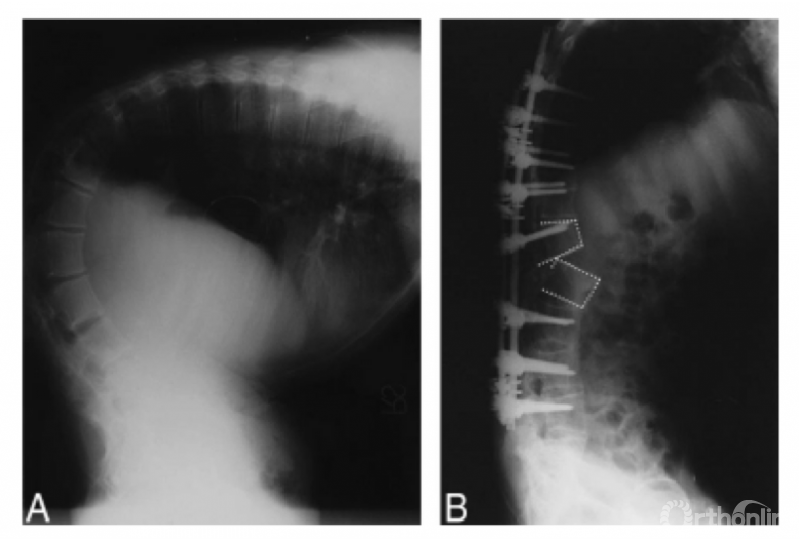

可调式手术体位架

张伟等采用自主设计的可调式手术体位架用于强直性脊柱炎重度后凸畸形后路截骨矫形。将传统手术床中的多点支撑改为软性、柔和曲面支撑,增加接触面积、减少局部受力,有效预防压疮等长时间俯卧位导致的相关并发症。

截骨闭合时仅需同步调整两侧对应的支撑杆,基本避免了传统手术中需要人工移除腹部衬垫及抬肩辅助矫形的繁琐操作,从根本上避免了由此带来的术区污染,明显降低了由于配合不慎导致截骨椎体发生矢状面移位、脊髓受压的风险。